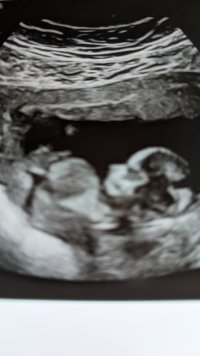

Trodde jeg skulle få svar på kjønnet på nipt testen men det gjorde jeg ikke![]()

følelsen er helt 50/50 nå